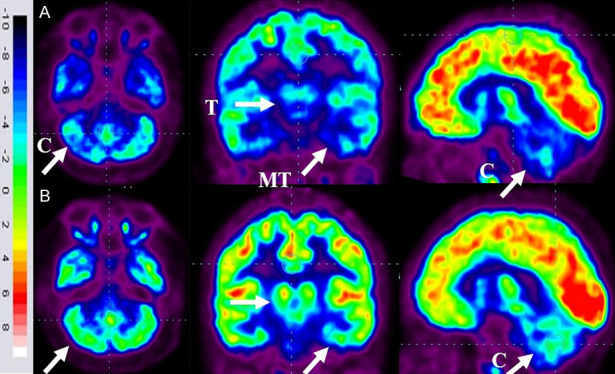

86名患者的家长同意在干预6个月后重复进行FDG-PET CT扫描以进行比较分析。干预前,这些患者的FDG-PET/CT扫描显示双侧内侧颞叶皮层、丘脑和小脑的代谢活动降低[代谢减退]。此外,它们还表现出尾状头、壳核、眶额皮质和前额叶皮质的代谢活动增加(代谢亢进)。

干细胞移植六个月后,所有患者的大脑活动均得到改善。此前,代谢低下区域[内侧颞叶皮质、丘脑和小脑]显示FDG摄取增加,而代谢亢进区域[尾状头、壳核、眶额皮质和前额叶皮质]显示FDG摄取减少(图6)。在进行T检验时,发现干预前后这些区域的平均SUV出现了统计学上的显着变化[P<0.05]。

A.顶行:标有箭头的蓝色区域表明代谢低下。B. 下排:用箭头标记的绿色区域表明细胞移植后新陈代谢得到改善。

FDG PET CT大脑扫描被用作接受多剂量细胞移植的患者的额外结果测量。它用于监测细胞水平干预的效果。这种功能性神经影像技术利用18-FDG来研究大脑的代谢活动。我们对86名患者进行了FDG PET CT扫描脑部的比较研究,结果证明了其对新陈代谢的平衡作用。代谢低下的区域显示代谢增加,而代谢亢进的区域显示代谢减少。